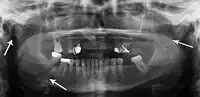

Plain film radiography

Traditionally, plain films of the mandible would be exposed but had lower sensitivity and specificity owing to overlap of structures. Views included AP (for parasymphsis), lateral oblique (body, ramus, angle, coronoid process) and Towne's (condyle) views. Condylar fractures can be especially difficult to identify, depending on the direction of condylar displacement or dislocation so multiple views of it are usually examined with two views at perpendicular angles.[11]

Towne's view of a bilateral condyle fracture. White arrow is a fracture on the neck of the condyle. Black arrow shows the condyle pulled to the medial. The same injury can be seen on the opposite side